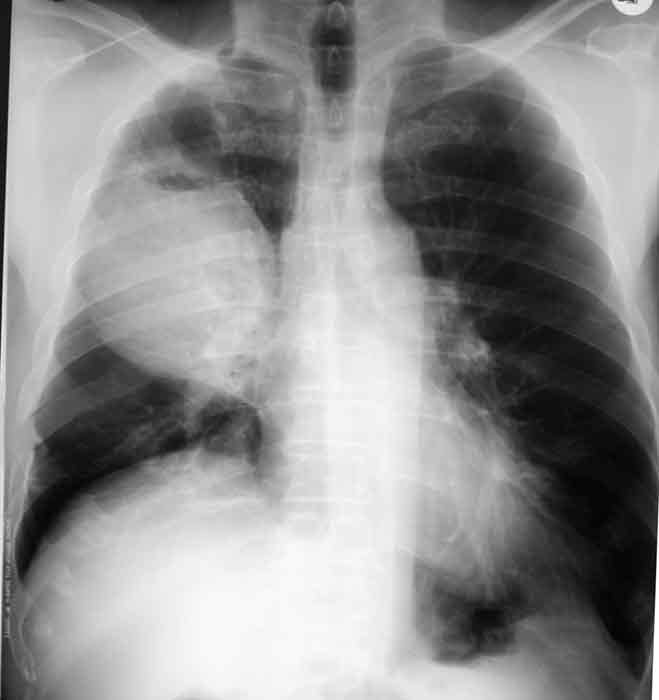

What is the name of the pathology as seen in this image?

Pneumothorax

What could the collapsed portion of lung tissue adjacent to the right side of the mediastinum also be known as?

Atelectasis